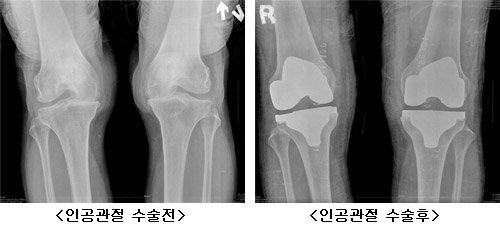

고령화로 인해 노인인구가 증가하면서 여러 가지 사회, 경제적 문제점들이 떠오르고 있다. 특히 건강과 관련된 것들에 많은 관심이 집중되는데, 노인들이 겪게 되는 여러 질병 중하나인 퇴행성 관절염이 노년의 삶의 질을 떨어뜨리는 주범이 되고 있다. 의학 기술의 발달과 경제적 풍요는 많은 사람들이 보다 쉬운 방법으로 여러 가지 질병의 고통에서 벗어나게 해주었다. 특히 인공 관절 수술은 말기 퇴행성 관절염 환자들에게 새로운 삶을 가져다주는 좋은 예라 할 수 있으며, 수술 후 만족도도 해가 갈수록 높아지는 추세다.

인공 관절 수술이 지속적인 재활 과정을 필요로 하는 통증이 큰 수술이지만 관절염 환자들에게 새로운 삶의 활력을 주는 점에서 눈여겨보아야 할 것이다. 의학기술의 발달과 의료진들의 노력으로 수술에 따른 통증은 과거에 비해 현저하게 줄어 통증 없는 인공 관절 수술이 가능해졌다고 말할 수 있다. 막연한 통증에 대한 두려움과 선입견을 버리고 한번쯤 의료진의 노력과 무통 기술의 발전에 귀 기울여 보는 것은 어떨까 생각해 본다.